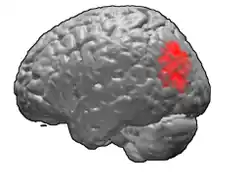

Brodmann area 39, or BA39, is part of the parietal cortex in the human brain. BA39 encompasses the angular gyrus, lying near to the junction of temporal, occipital and parietal lobes.

This area is also known as angular area 39 (H). It corresponds to the angular gyrus surrounding the caudal tip of the superior temporal sulcus. It is bounded dorsally approximately by the intraparietal sulcus. In terms of its cytoarchitecture, it is bounded rostrally by the supramarginal area 40 (H), dorsally and caudally by the peristriate area 19, and ventrally by the occipitotemporal area 37 (H) (Brodmann-1909).